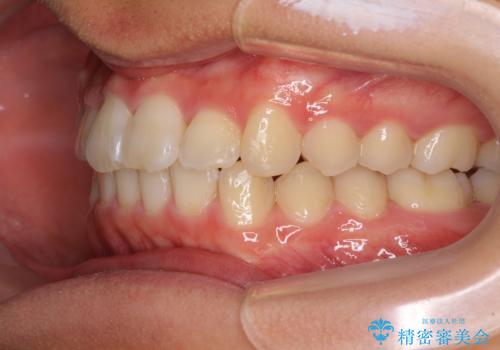

深い咬み合わせとデコボコ ワイヤー矯正で短期治療

- 前歯のデコボコを改善したいとのことで来院された患者様です。

インビザラインでの治療も可能でしたが、深い咬み合わせと奥歯の咬み合わせを改善するにあたり、ワイヤー矯正の方が治療期間を短縮できると判断し、ワイヤー矯正をお勧めしました。

結果として、1年かからずに奥歯の咬み合わせを改善することができました。